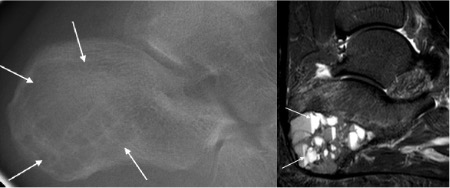

Aneurysmal bone cyst

- Usually in patients <30 years

- Sponge-like cyst with blood-filled spaces and fibrous septae; may arise as the result of a vascular anomaly

- Seen as radiolucent, often rapidly expansile lesion with a thin cortical shell

- Matrix fluid-fluid levels on MRI are typical

Aneurysmal bone cyst with fluid-fluid levels on MRI